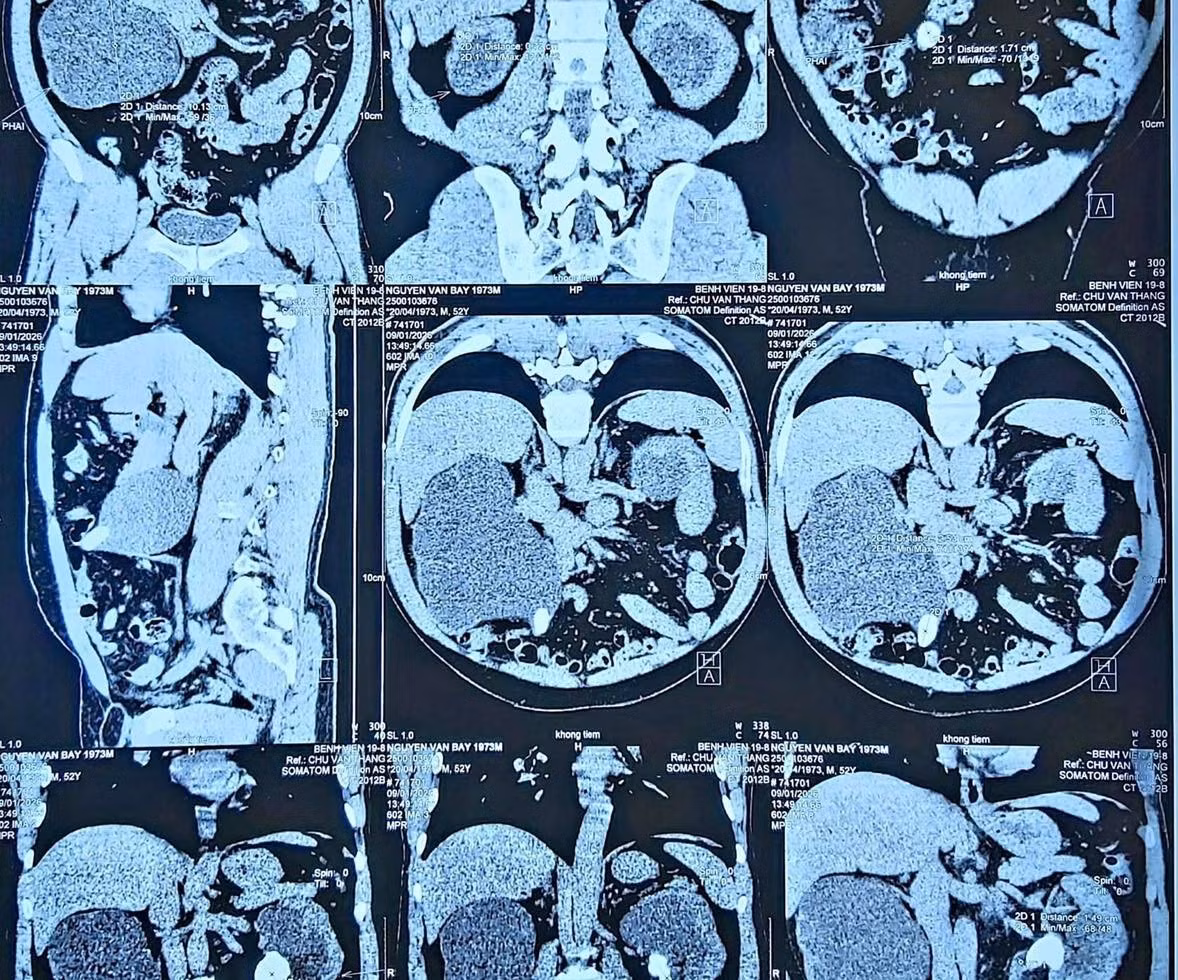

Thận ứ nước vì sỏi trên phim chụp - Ảnh BVCC

Kết quả thăm khám cho thấy: Ứ nước thận trái độ IV; Ứ nước thận phải độ III; Suy thận cấp do sỏi hai thận gây tắc nghẽn.

Trên phim CT: Thận trái giãn mỏng, gần như mất hoàn toàn chức năng; Thận phải còn hoạt động, nhưng đã suy giảm nặng.

Trên phim chụp CT: Thận trái giãn mỏng, gần như mất hoàn toàn chức năng; Thận phải còn hoạt động, nhưng đã suy giảm nặng - Ảnh BVCC